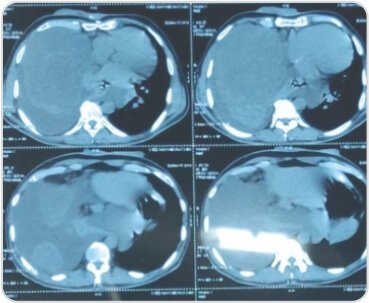

CT scan showed two large heterogenously enhancing pleural based soft tissue density lesions with neovascularity in right hemithorax measuring 14.3×13.4×11.5cm and 7.9×7.5×6.1cm. Surgery – Pleural aspiration was done and 2 litres of fluid was drained. Patient developed hemodynamic instability and was resuscitated in OT. Right posterolateral thoracotomy was performed and the tumor was removed under VATS

CT scan showing solitary fibrous right pleural tumor